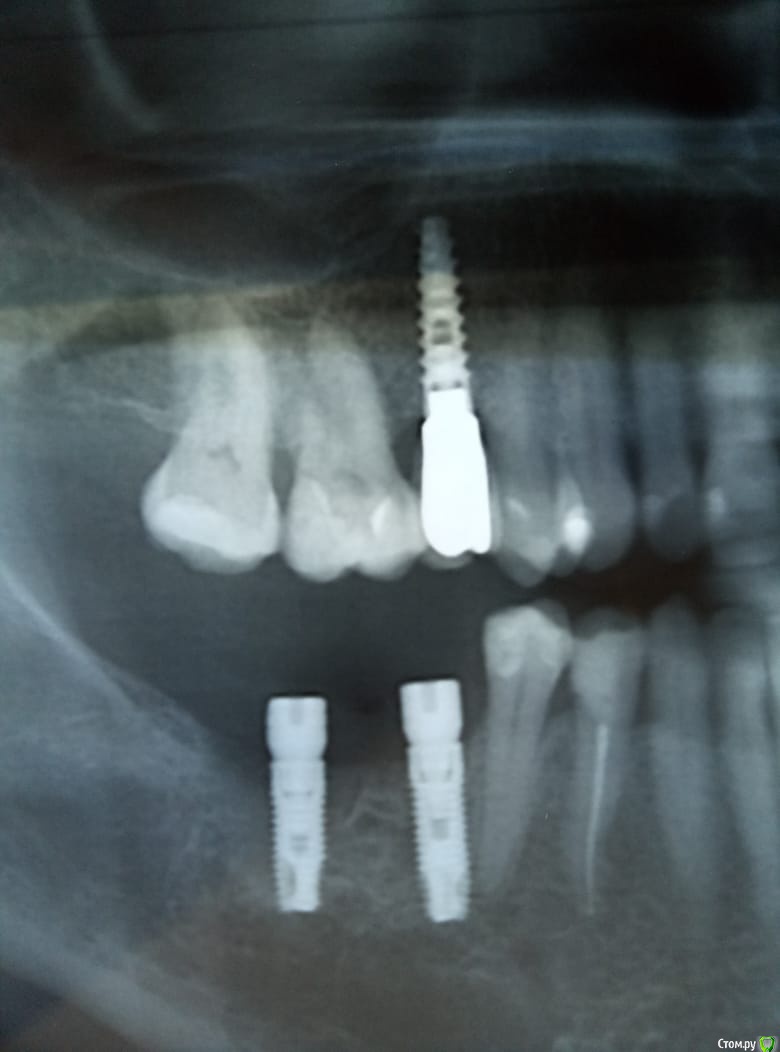

dave09090 Опубликовано 22 октября, 2018 Поделиться Опубликовано 22 октября, 2018 Думаю что нужно выкручивать 46 имплант. Как считаете ? Ссылка на комментарий

dave09090 Опубликовано 23 октября, 2018 Автор Поделиться Опубликовано 23 октября, 2018 Боли постоянного характера , иррадиация в 44 . Ссылка на комментарий

dave09090 Опубликовано 23 октября, 2018 Автор Поделиться Опубликовано 23 октября, 2018 Простите в 45 . Нет перфорации 45 зуба ? Ссылка на комментарий

Lodkin666 Опубликовано 23 октября, 2018 Поделиться Опубликовано 23 октября, 2018 Пломба на 45 не маленькая, может быть совпало с обострением хронического пульпита 45? Ссылка на комментарий

dok1 Опубликовано 23 октября, 2018 Поделиться Опубликовано 23 октября, 2018 У меня было подобное. Между имплантом и зубом 45 около трёх мм. Идеально параллельно. И пульпит. Прям почти периодонтит. Даже подвижность появилась. Зуб абсолютно интактен. До нерва снизу более 3 мм. Пролечил канал. Видимо сосуд, идущий к апексу пересечён имплантом. Пришлось депульпировать. Сделал вывод - в этой жизни бывает всё 2 Ссылка на комментарий

Тимур86 Опубликовано 23 октября, 2018 Поделиться Опубликовано 23 октября, 2018 Там вроде апекс загибается аккурат в проекции имплантата,может быть и шлифанули... Ссылка на комментарий

___49___ Опубликовано 24 октября, 2018 Поделиться Опубликовано 24 октября, 2018 (изменено) Разберите возможные варианты исхода данной ситуации .1- переход в периодонтит с вовлечением импланта ( на выход имплант , зуб под?)2- зуб жив , все счастливы (пробы на витальность ) , но в будущем могут быть проблемы, как юридические так и клинические . 3- эндодонтия ( не исключает обсеменение, а также попадание инородного на поверхность импланта) , но опять таки могут быть проблемы как клинические так и юридические по прошествии времени . 4 - перекрутить , зуб контролить на витальность (максимальное зло - убьете зуб) Мне больше нравиться 4 вариант . может тему в закрытый? Изменено 24 октября, 2018 пользователем ___49___ Ссылка на комментарий